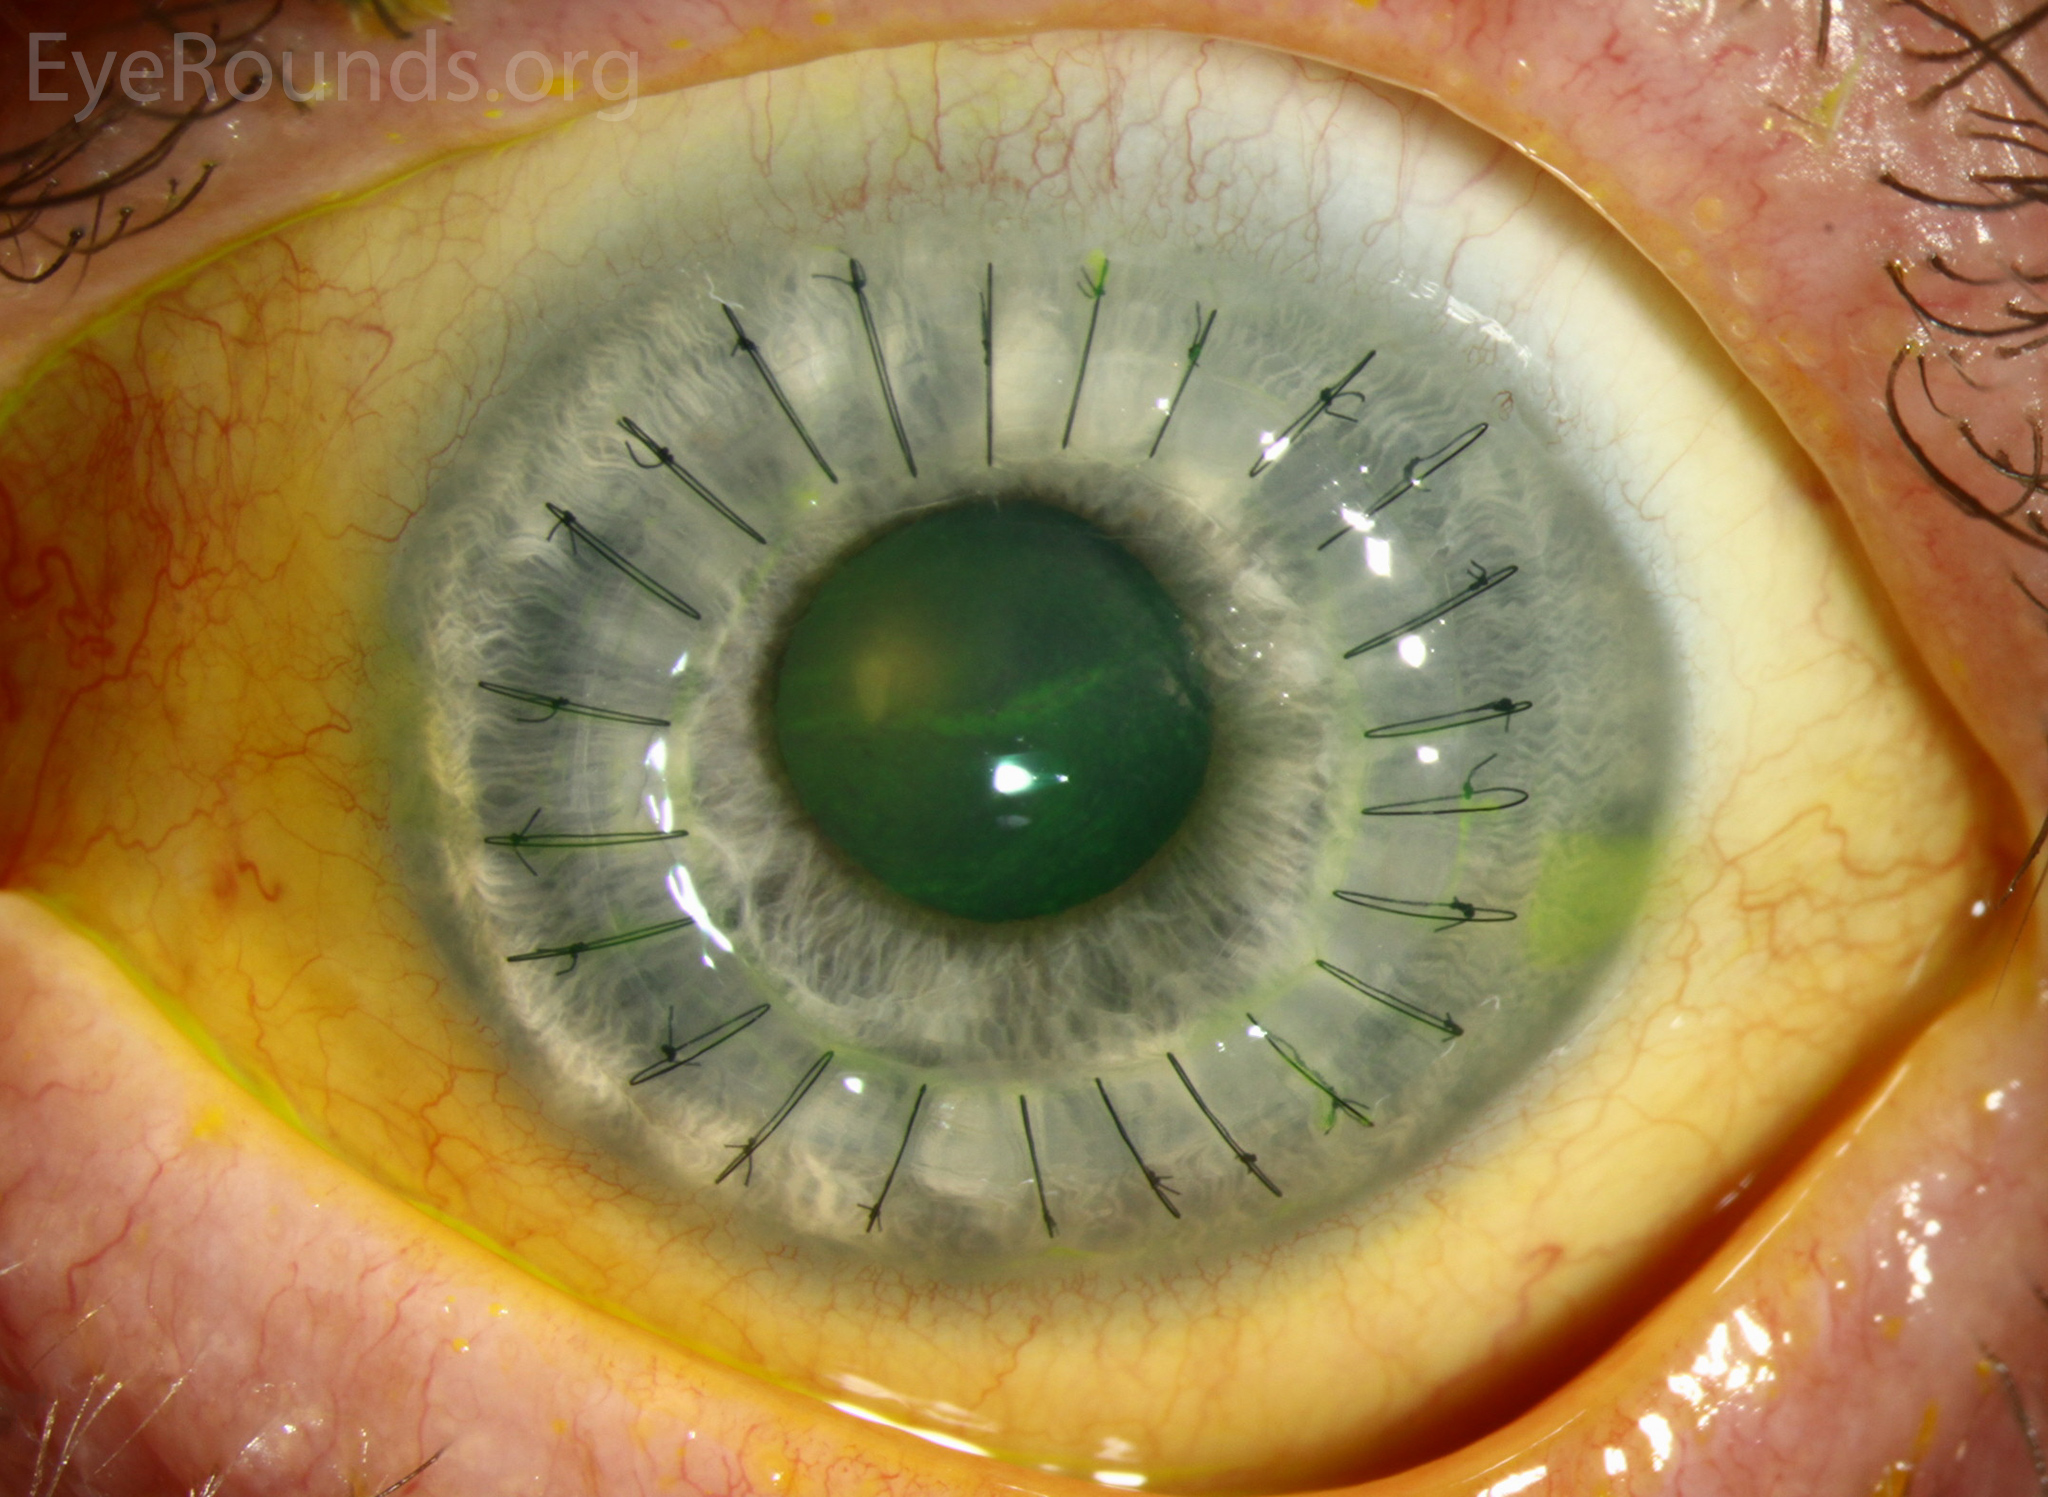

PK is a full-thickness transplant procedure, in which a trephine of an appropriate diameter is used to make a full-thickness resection of the patient's cornea, followed by placement of a full-thickness donor corneal graft. Interrupted and/or running sutures are placed in radial fashion at equal tension to minimize post-operative astigmatism (Figure 2). Later, the sutures are removed selectively to reduce the amount of astigmatism present. A transplant can last decades with proper care (Figure 3). While once the most prominent type of corneal transplant, PK has been supplanted by partial thickness techniques for endothelial dysfunction without significant stromal scarring. PKs are performed primarily for visually significant stromal scarring, opacities with an uncertain status of the endothelium or significant posterior corneal involvement, corneal ectasia (such as keratoconus and pellucid marginal degeneration, especially if there is history of hydrops), combined stromal and epithelial disease (such as Peters anomaly), and infectious or non-infectious corneal ulcerations or perforations (1, 14). A variant of the procedure, the mini-PK, can be used to treat more focal defects in the cornea (Figure 4).

However, postoperative recovery time is relatively long, sometimes taking years to achieve best-corrected visual acuity. Frequently, there is substantial postoperative refractive error due to high regular or irregular astigmatism of the graft, and a higher chance of requiring rigid gas permeable contact lens wear to correct astigmatic error. There is a higher risk of allograft rejection compared with other keratoplasty types. Additionally, PKs carry a higher lifetime risk of wound dehiscence due to the compromised tectonic strength that comes from a full-thickness wound.